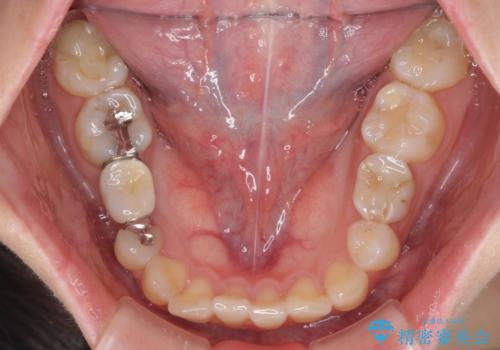

欠損と残存乳歯 矯正治療とインプラント治療

- 残存した乳歯や歯の欠損、歯並びを気にして来院された患者様です。

乳歯を残した状態は予後がよくないこと、矯正治療と補綴治療を総合的に進めていきたいとのことで、インビザラインによる矯正治療とインプラント補綴治療を並行して進めていくこととしました。